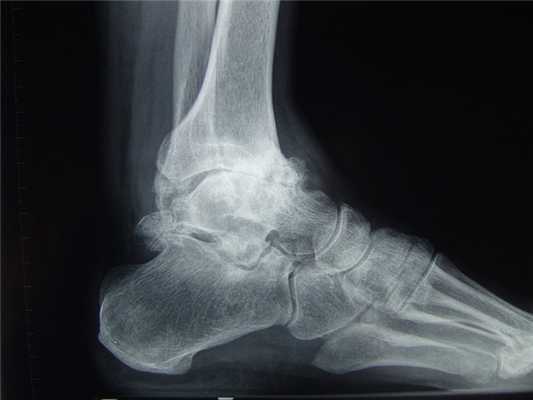

Остеоартроз голеностопного сустава на рентгене.

Основной причиной артроза голеностопного сустава (крузартроза) является травматическое повреждение его анатомических структур — таранной и большеберцовой кости, внутренней или наружной лодыжек. Реже болезнь развивается вследствие поражения голеностопа ревматоидным артритом. И еще реже артроз возникает спонтанно, в результате дегенеративно-дистрофических изменений в хрящевой и костной тканях.

Остеоартроз левого(справа на снимке) голеностопного сустава